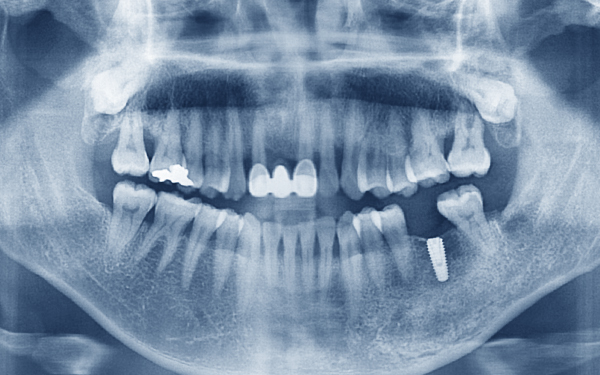

아래턱 뼈 안에는 “하치조신경“ 이라는 큰 신경이 좌우에 1개씩 있습니다.

아래 어금니 부위에 임플란트를 심을 때, 잇몸뼈와 하치조신경 사이의 거리를 정확히 계산해야 신경이 손상되는 것을 막을 수 있습니다.

잘못된 시술로 인해 신경이 손상된다면, 해당 부위의 감각이 마비되거나 간지러운 증상 등이 나타날 수 있어 주의해야 합니다. -

위턱의 코를 기준으로 좌우에 상악동이라는 빈 공간이 있습니다.

윗 어금니에 임플란트를 심을 때, 잇몸뼈와 상악동 사이의 거리를 정확히 계산해야 상악동에 염증이 생기는 것을 막을 수 있습니다.

과거 축농증이나 비염을 앓은 적이 있거나 어금니 뿌리 염증이 심했던 경우에는 상악동에 염증이 발생한 경우가 많습니다.

윗니와 아랫니가 맞물리는 것을 “교합"이라고 합니다.

교합이 좋아야 잘 씹을 수 있고, 임플란트를 불편함 없이 오랫동안 사용할 수 있습니다.

이를 위해서는 임플란트 수술 시, 환자마다 잇몸뼈의 형태를 고려하여 최적의 치아 각도를 계산하여 진행해야 합니다.